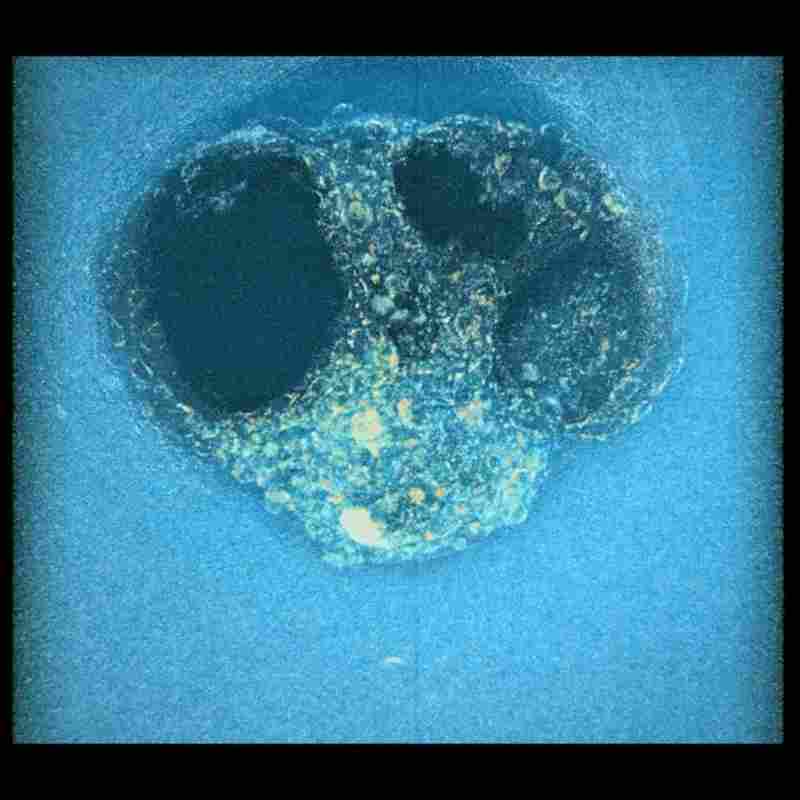

西班牙巴塞罗那生物工程研究所的研究团队通过延时摄影技术,首次完整记录了人类胚胎植入子宫内膜的力学过程。该成果发表于《科学进展》(Science Advances)期刊,为人类生殖研究提供了突破性视角。

由于胚胎植入过程发生在母体内部,传统技术难以直接观察。为此,研究团队开发了一种高仿真子宫模型,采用富含胶原蛋白和胚胎发育必需蛋白质的凝胶材料模拟真实子宫内膜。实验中,人类胚胎被放置于凝胶附近,研究人员每20分钟通过显微镜拍摄一次,持续16至24小时,最终合成动态影像。

结果显示,人类胚胎会主动拉扯子宫内膜组织,通过机械力和酶的共同作用嵌入子宫内壁。这一过程速度远超预期,且与小鼠胚胎仅黏附在子宫表面的方式截然不同。密歇根州立大学的专家指出,这是首次详细揭示胚胎植入的力学机制,但子宫如何对胚胎施加反作用力仍需进一步研究。

该技术为探索胚胎着床失败等生殖问题提供了新工具。未来,团队计划延长观察周期,分析更长时间的力学分布,以深入理解植入机制。这一突破不仅填补了人类发育研究的空白,也为辅助生殖技术的优化提供了科学依据。